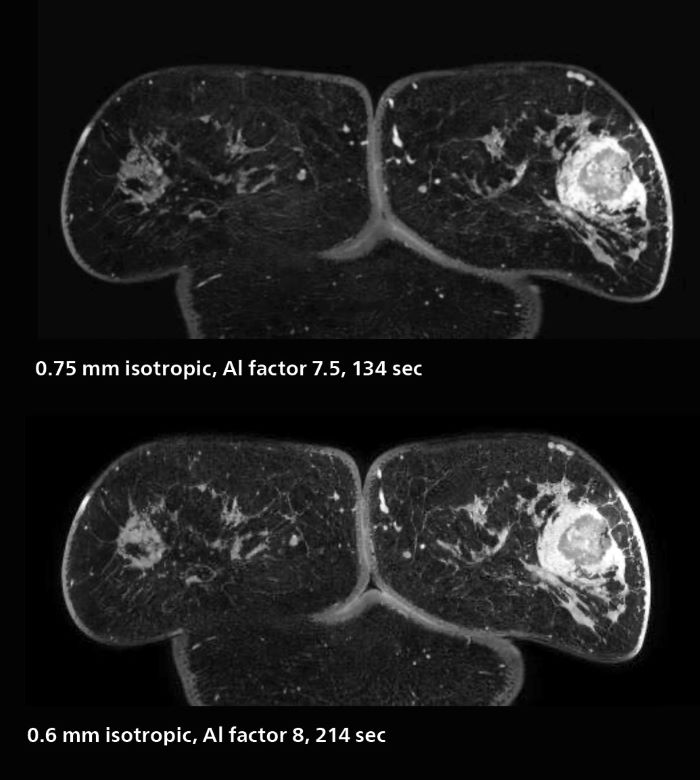

3D MRI of breast cancer

Scanning was performed with two different voxel sizes. AI enabled volume MRI allows image reconstruction in other directions. Biopsy revealed invasive ductal carcinoma in this patient. Performed on Elition X.

Fast AI-enabled MRI of breast cancer: comparing 3D acquisitions with 0.75 mm and 0.6 mm isotropic voxels.

The hospital’s routine ExamCards for breast imaging include:

• ExamCard for 0.7 mm isotropic, 2:09 min, acceleration factor 7.5

• ExamCard for 0.6 mm isotropic, 3:37 min, acceleration factor 8

Speed and high image quality are also important factors determining the diagnostic value of breast MRI. “When the spatial resolution is not high enough for making the diagnosis of breast cancer, a very difficult decision must be made,” says Dr. Katahira. “Since SmartSpeed now allows us to increase the resolution, we can often easily provide a confident answer. In the past with SENSE we used 1.2 mm isotropic voxels in breast imaging after contrast admission. With Compressed SENSE that is 0.8 mm. Now with SmartSpeed we can acquire 0.6 mm isotropic voxels and the images are so clear that even tiny details are clearly visible.”